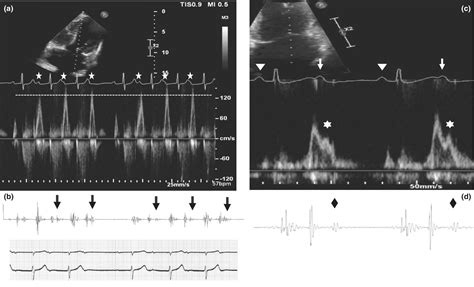

To understand the Atrial Kick, one must first visualize the cardiac cycle. The heart consists of four chambers: two upper chambers called atria and two lower chambers called ventricles. During the filling phase of the heart (diastole), blood flows passively from the atria into the ventricles through open valves. This passive filling accounts for approximately 70% to 80% of the total ventricular volume.

The Atrial Kick represents the final 20% to 30% of blood that is pushed into the ventricles during the late stage of diastole. This occurs when the atria contract—triggered by electrical signals from the sinoatrial (SA) node—forcing the remaining blood through the atrioventricular valves. Although it may seem like a small percentage, this "kick" is vital for maintaining optimal cardiac output, especially during periods of physical exertion or when the heart is already under stress.

Why does that last 20% of blood matter so much? In a healthy individual, the Atrial Kick acts as a reserve, ensuring that the ventricles are fully primed before they contract to send blood to the rest of the body. This increased volume stretches the ventricular walls, which in turn leads to a more forceful contraction, a principle known as the Frank-Starling law of the heart.